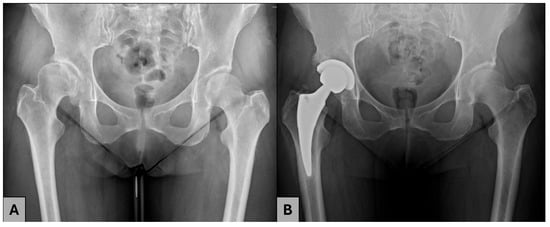

Impact of Prior Periacetabular Osteotomy on Total Hip Arthroplasty Outcomes in Patients with Developmental Dysplasia of the Hip